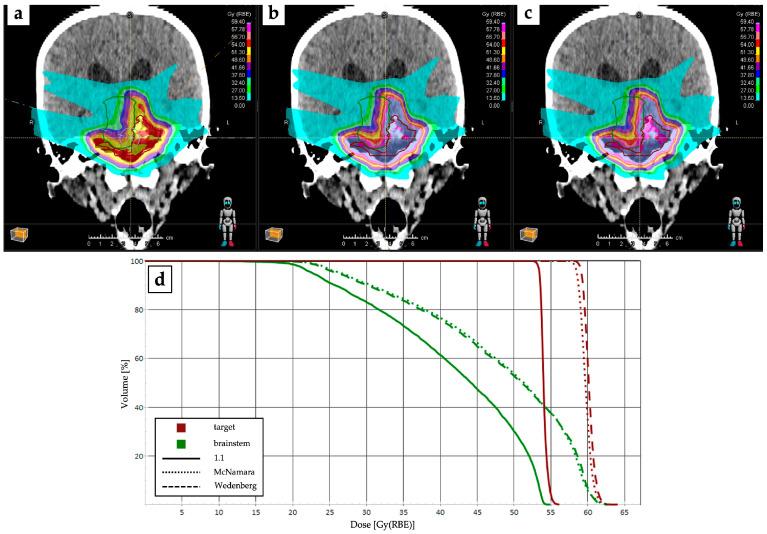

头颈部癌质子治疗的现状与未来方向

Current Status and Future Directions of Proton Therapy for Head and Neck Carcinoma.

The growing interest in proton therapy (PT) in recent decades is justified by the evidence that protons dose distribution allows maximal dose release at the tumor depth followed by sharp distal dose fall-off. But, in the holistic management of head and neck cancer (HNC), limiting the potential of PT to a mere dosimetric advantage appears reductive. Indeed, the precise targeting of PT may help evaluate the effectiveness of de-escalation strategies, especially for patients with human papillomavirus associated-oropharyngeal cancer (OPC) and nasopharyngeal cancer (NPC). Furthermore, PT could have potentially greater immunogenic effects than conventional photon therapy, possibly enhancing both the radiotherapy (RT) capability to activate anti-tumor immune response and the effectiveness of immunotherapy drugs. Based on these premises, the aim of the present paper is to conduct a narrative review reporting the safety and efficacy of PT compared to photon RT focusing on NPC and OPC. We also provide a snapshot of ongoing clinical trials comparing PT with photon RT for these two clinical scenarios. Finally, we discuss new insights that may further develop clinical research on PT for HNC.

摘要